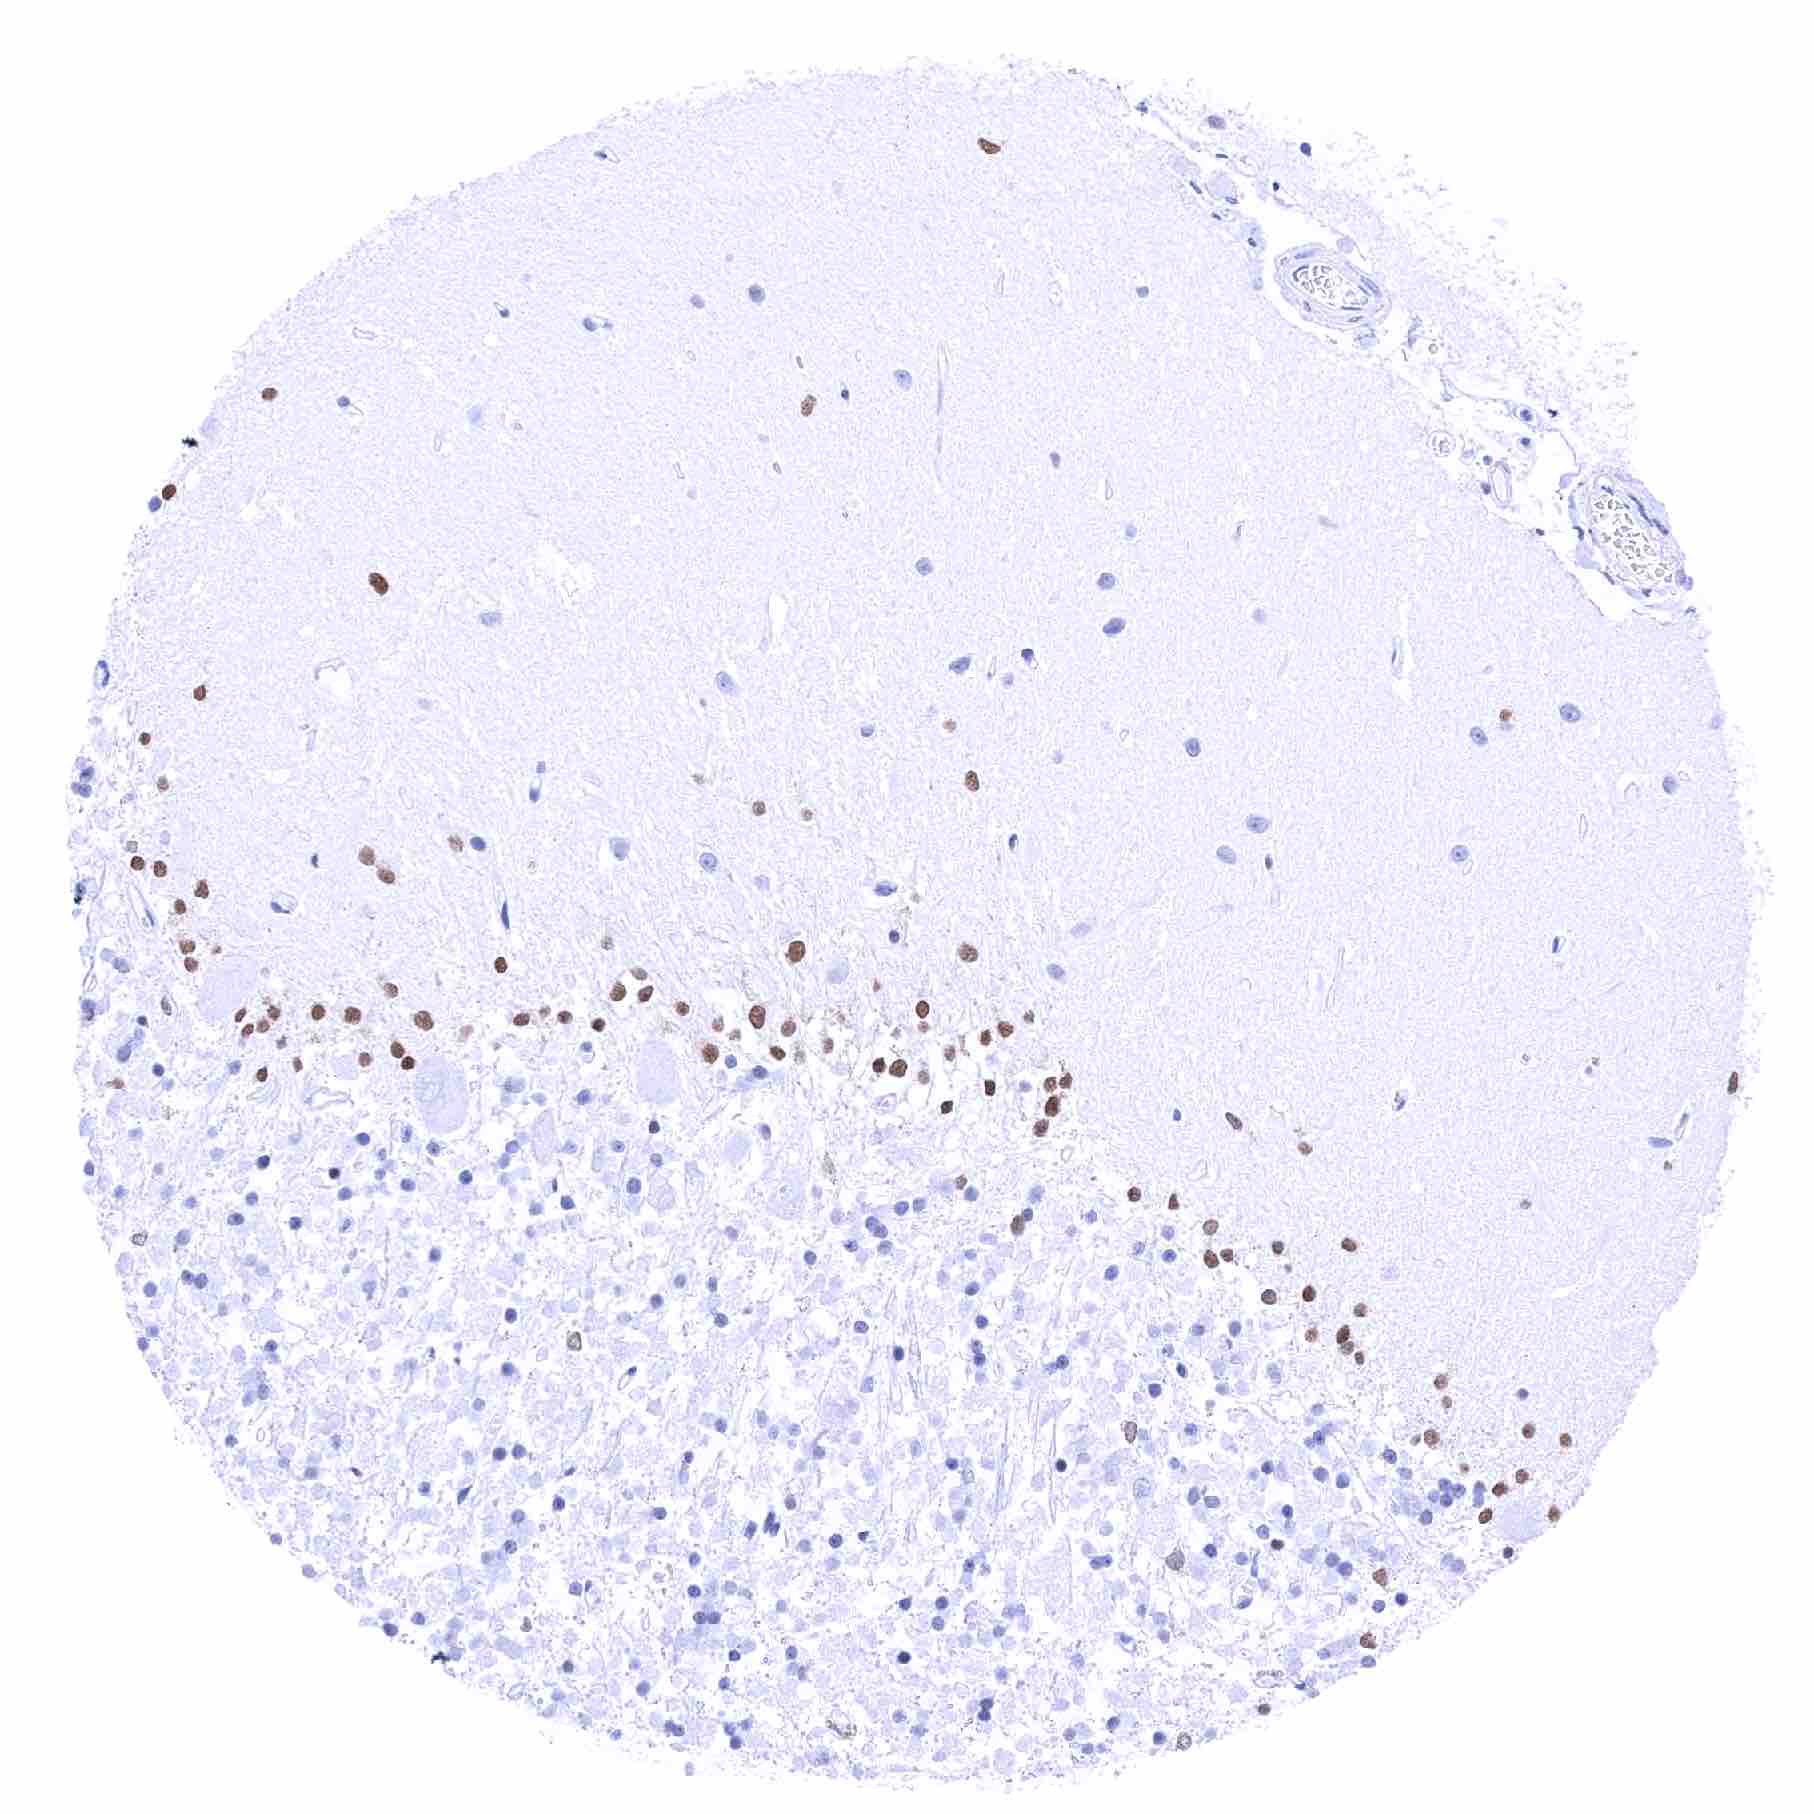

Cerebrum, grey matter – Moderate to strong SOX2 positivity of a fraction of glial cells